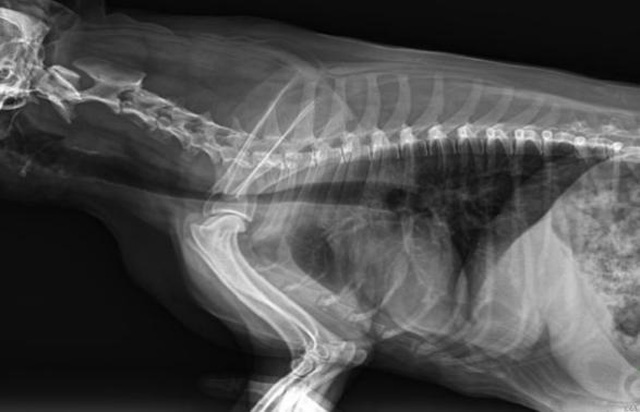

寵物DR是動物專用的數字化攝影系統,x線的穿透能力、低的輻射劑量,輻射劑量比X光低:熒光作用和感光作用,可以穿透動物身體的結構顯示成像,動物的各個部位成像輔助獸醫(yī)診療。寵物DR采集時間10ms以下,成像時間僅為3秒,從檢查到出診斷報告大約5—10分鐘。較高的空間分辨力和低噪聲率,可獲得高清晰圖像。 DR成像數字化處理的特點可進行后處理。提高了病灶的檢出率,這樣大大提高檢查的準確率提高診斷準確率避免漏診誤診等情況。